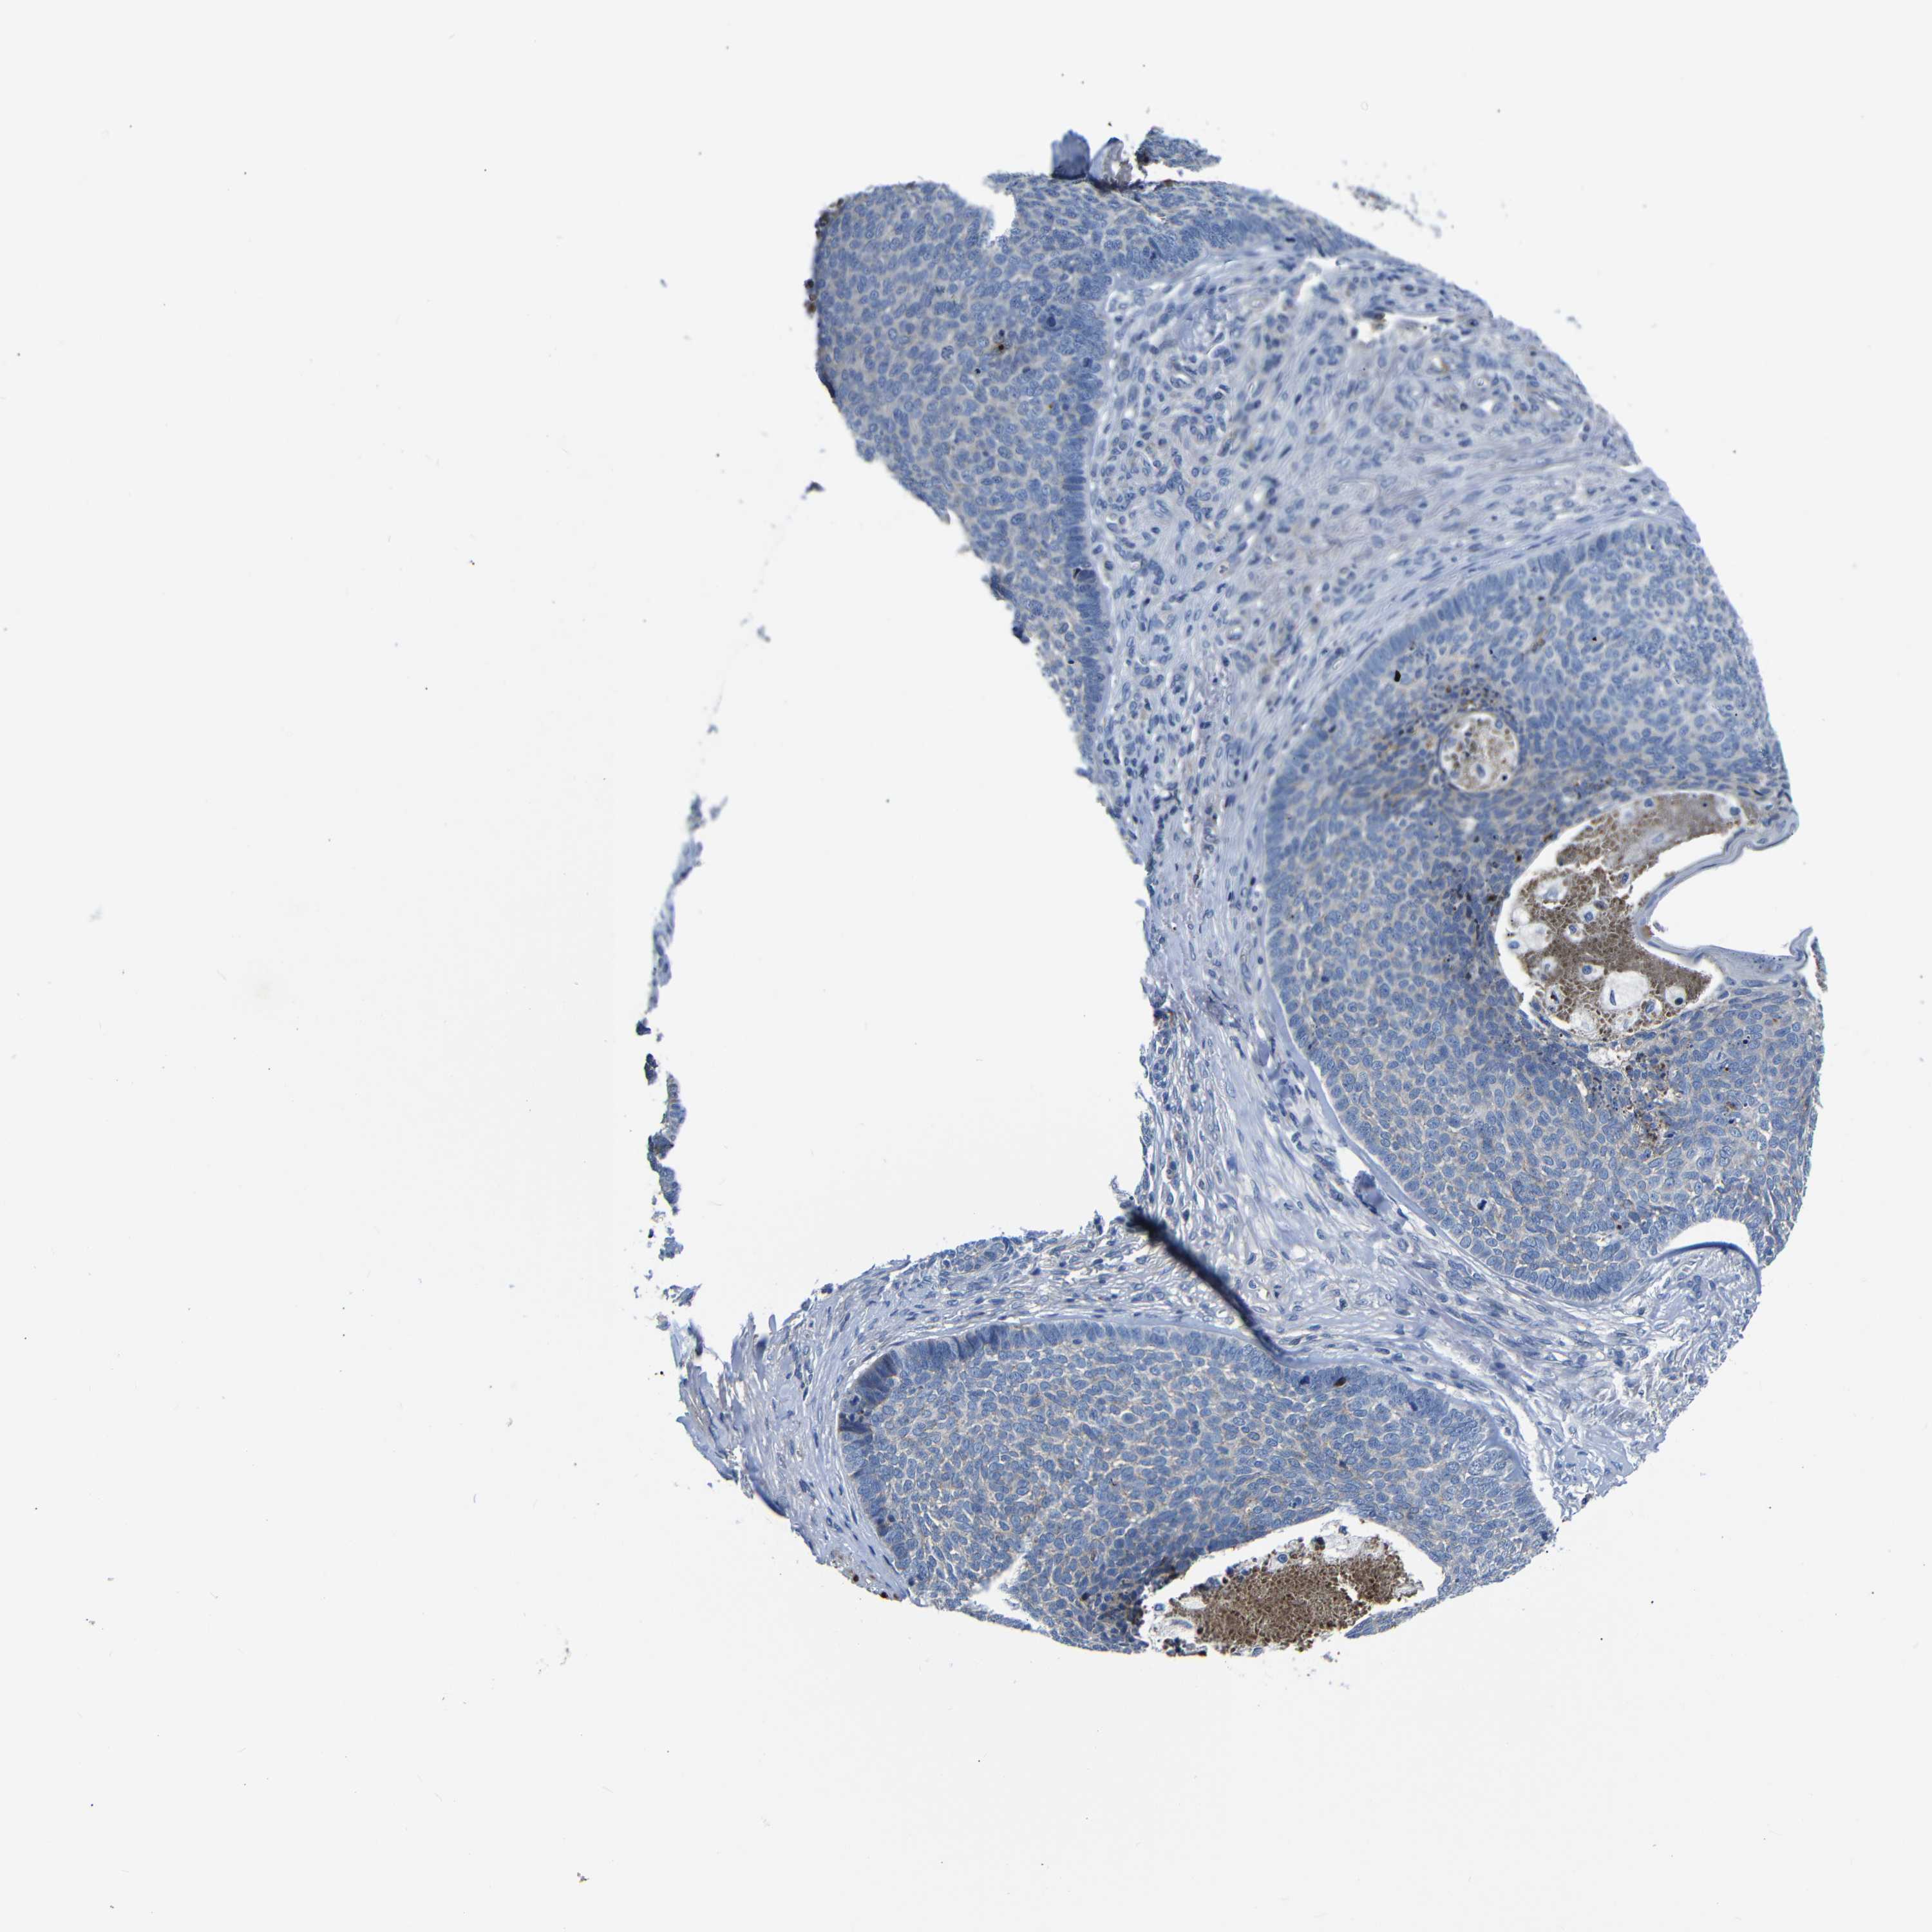

SKIN CANCER - Protein expressioni

A mouse-over function shows sample information and annotation data. Click on an image to view it in a full screen mode. Samples can be filtered based on level of antibody staining by selecting one or several of the following categories: high, medium, low and not detected. The assay and annotation is described here.

Each image is clickable and will lead to virtual microscopy that enables deeper exploration of all samples and also displays staining intensity scores, fraction scores and subcellular localization as well as patient and tissue information for each sample.

HPA030212

HPA030213

HPA030214

HPA030215

CAB013496

Staining

High

Medium

Low

Not detected

Intensity

Strong

Moderate

Weak

Negative

Quantity

>75%

75%-25%

<25%

None

Location

Nuclear

Cytoplasmic/membranous

Cytoplasmic/membranous,nuclear

Basal cell carcinoma

Squamous cell carcinoma, NOS

Squamous cell carcinoma, metastatic, NOS

Adnexal tumor, benign